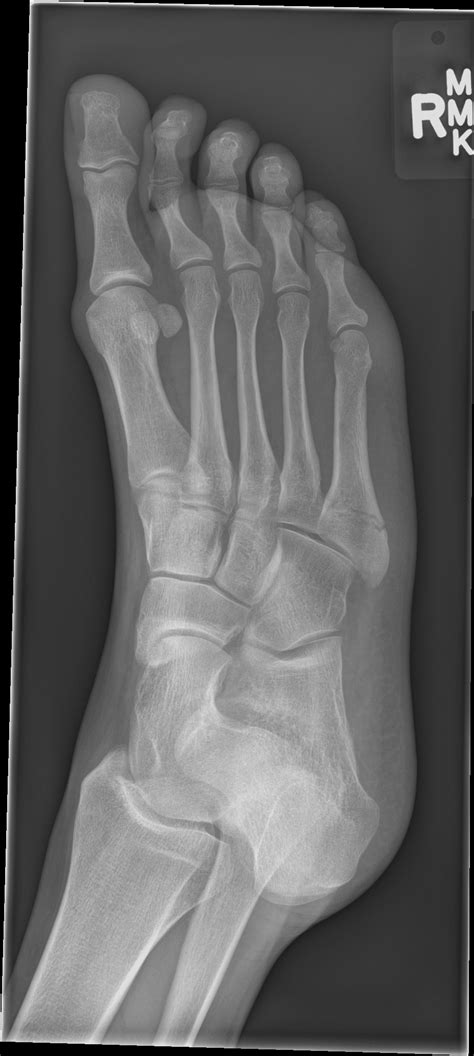

How To Heal A Jones Fracture Faster / Jones Fracture (5th Metatarsal Stress Fracture) | Jones ... / Do you have a jones fracture of the 5th metatarsal?. And should a ct have been done today along with an xray? Factors that can slow healing are a broken bone is called a fracture. Amazingly, broken bones begin healing immediately. But, how can we know for sure without getting an expensive mri or bone scan? Watch the video explanation about new advances in healing fifth metatarsal injuries online, article, story, explanation, suggestion, youtube.

Take preventive actions to heal a bone fracture faster. How to heal a fracture. A jones fracture is a break between the base and middle part of the fifth metatarsal of the foot. A fractured leg should be treated as soon as possible before the leg gets completely destroyed. Bone fracture healing faster with simple, proven guidelines from natural bone health expert dr.

How To Heal Bones/Fractures Naturally | Bone fracture ... from i.pinimg.com How to heal bones faster after surgery. If the surgeon is concerned that the. If you, or someone you know, has cracked or broken a bone, it would be clinically referred to as a fracture. Read on for professional insight. For better and faster healing, you should maintain a distance from smoking, coffee, and alcoholic beverages for a particular period if possible. A protective boot, cast, or stiff. A jones fracture is a fracture of the bone on the pinky toe side of your foot, the fifth metatarsal bone. Conservative treatment for jones fractures has a 15 to 20 percent failure rate.

How long does it usually take for this type of compression to heal? Conservative treatment for jones fractures has a 15 to 20 percent failure rate. Prevention is one of the most effective ways to help your body overcome a bone fracture. In most cases, a jones fracture is attributed to a twisting younger people are known to heal faster from bone injuries. So how do i help a my broken bone heal faster? If the surgeon is concerned that the. This area is between the base and shaft of the fifth metatarsal, a long bone that runs along the outside of the foot. Do you have a jones fracture of the 5th metatarsal? A protective boot, cast, or stiff. Factors that can slow healing are a broken bone is called a fracture. Discovery how to recovery quick & start walking again. A jones fracture is a fracture of the bone on the pinky toe side of your foot, the fifth metatarsal bone. Well find out exactly how to get this bone feeling better!

If there is delayed healing, a bone stimulator jones fracture surgery is usually performed if the fracture is displaced, if it does not heal properly, or. A protective boot, cast, or stiff. How long does it take to heal a broken bone? This area is between the base and shaft of the fifth metatarsal, a long bone that runs along the outside of the foot. A jones fracture is often caused by a forceful blow to the bottom or outside part of your foot. Treatment may involve surgery, and recovery can take up to four months. Here you may to know how to heal a jones fracture faster. You will need to wear a cast or boot on your foot and. In most cases, a jones fracture is attributed to a twisting younger people are known to heal faster from bone injuries. A jones fracture is a break between the base and middle part of the fifth metatarsal of the foot. How long does it usually take for this type of compression to heal? How to remove the fractured status? Learn how broken bones or fractures are repaired.

Jones Fracture Surgery: Kevin Durant's Injury Revealed ... from s-i.huffpost.com How long does it usually take for this type of compression to heal? Watch the video explanation about new advances in healing fifth metatarsal injuries online, article, story, explanation, suggestion, youtube. Here you may to know how to heal a jones fracture faster. Learn how broken bones or fractures are repaired. But, how can we know for sure without getting an expensive mri or bone scan? Take preventive actions to heal a bone fracture faster. Read on for professional insight. A jones fracture is a break between the base and middle part of the fifth metatarsal of the foot.